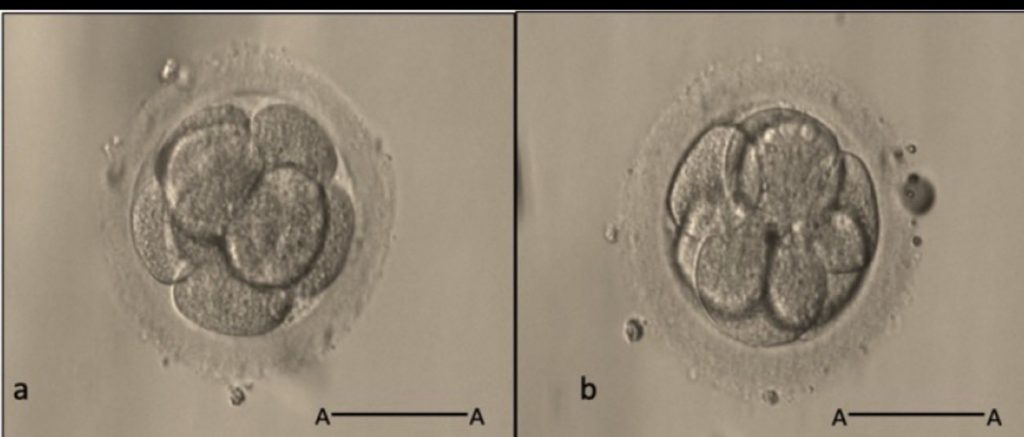

胚胎品質評估是決定選擇D3或D5移植的關鍵依據之一。

一般而言,胚胎在D3階段若數量充足、細胞數和形態評分優良,則可考慮延長培養至D5以篩選發育潛力最佳的囊胚;

D3移植適用品質標準

• 胚胎數量少或品質不理想

若僅有1-3顆D3胚胎,細胞數少於8、分裂不均、形態評分為C級

(>20%碎片、非對稱分裂),則不建議繼續延長培養,直接移植可避免胚胎流失。

• D3細胞數低於10顆

D3時胚胎細胞數愈多(≥10顆),愈有潛力發展至優質D5囊胚。

低於6-8顆細胞的胚胎較難成功形成囊胚,可考慮D3直接移植.

• 胚胎碎片多或分裂不良

高碎片率、細胞大小明顯不均一也屬品質偏低,不適合D5長培養.

• Morphological Grading

D3以細胞數(多於8顆者較佳)、碎片比例、胚胎分裂均勻性為主要指標。